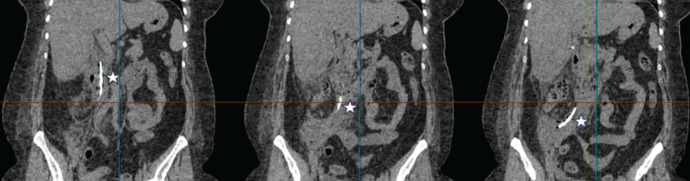

Endoscopic biliary stenting is a widely adopted technique for managing bile duct injuries post-cholecystectomy. However, its complications can have severe consequences. Although rare compared to other endoscopic retrograde cholangiopancreatography-related complications, duodenal perforation due to stent migration carries a significant risk of morbidity and mortality. While biliary stenting is often considered a less invasive alternative to surgery, timely recognition and management of potential complications remain crucial. We present a case of duodenal perforation due to biliary stent migration in a 49-year-old woman following laparoscopic cholecystectomy, emphasizing the effectiveness of conservative management, including the key role of interventional radiology, in selected patients.

Abstract Image